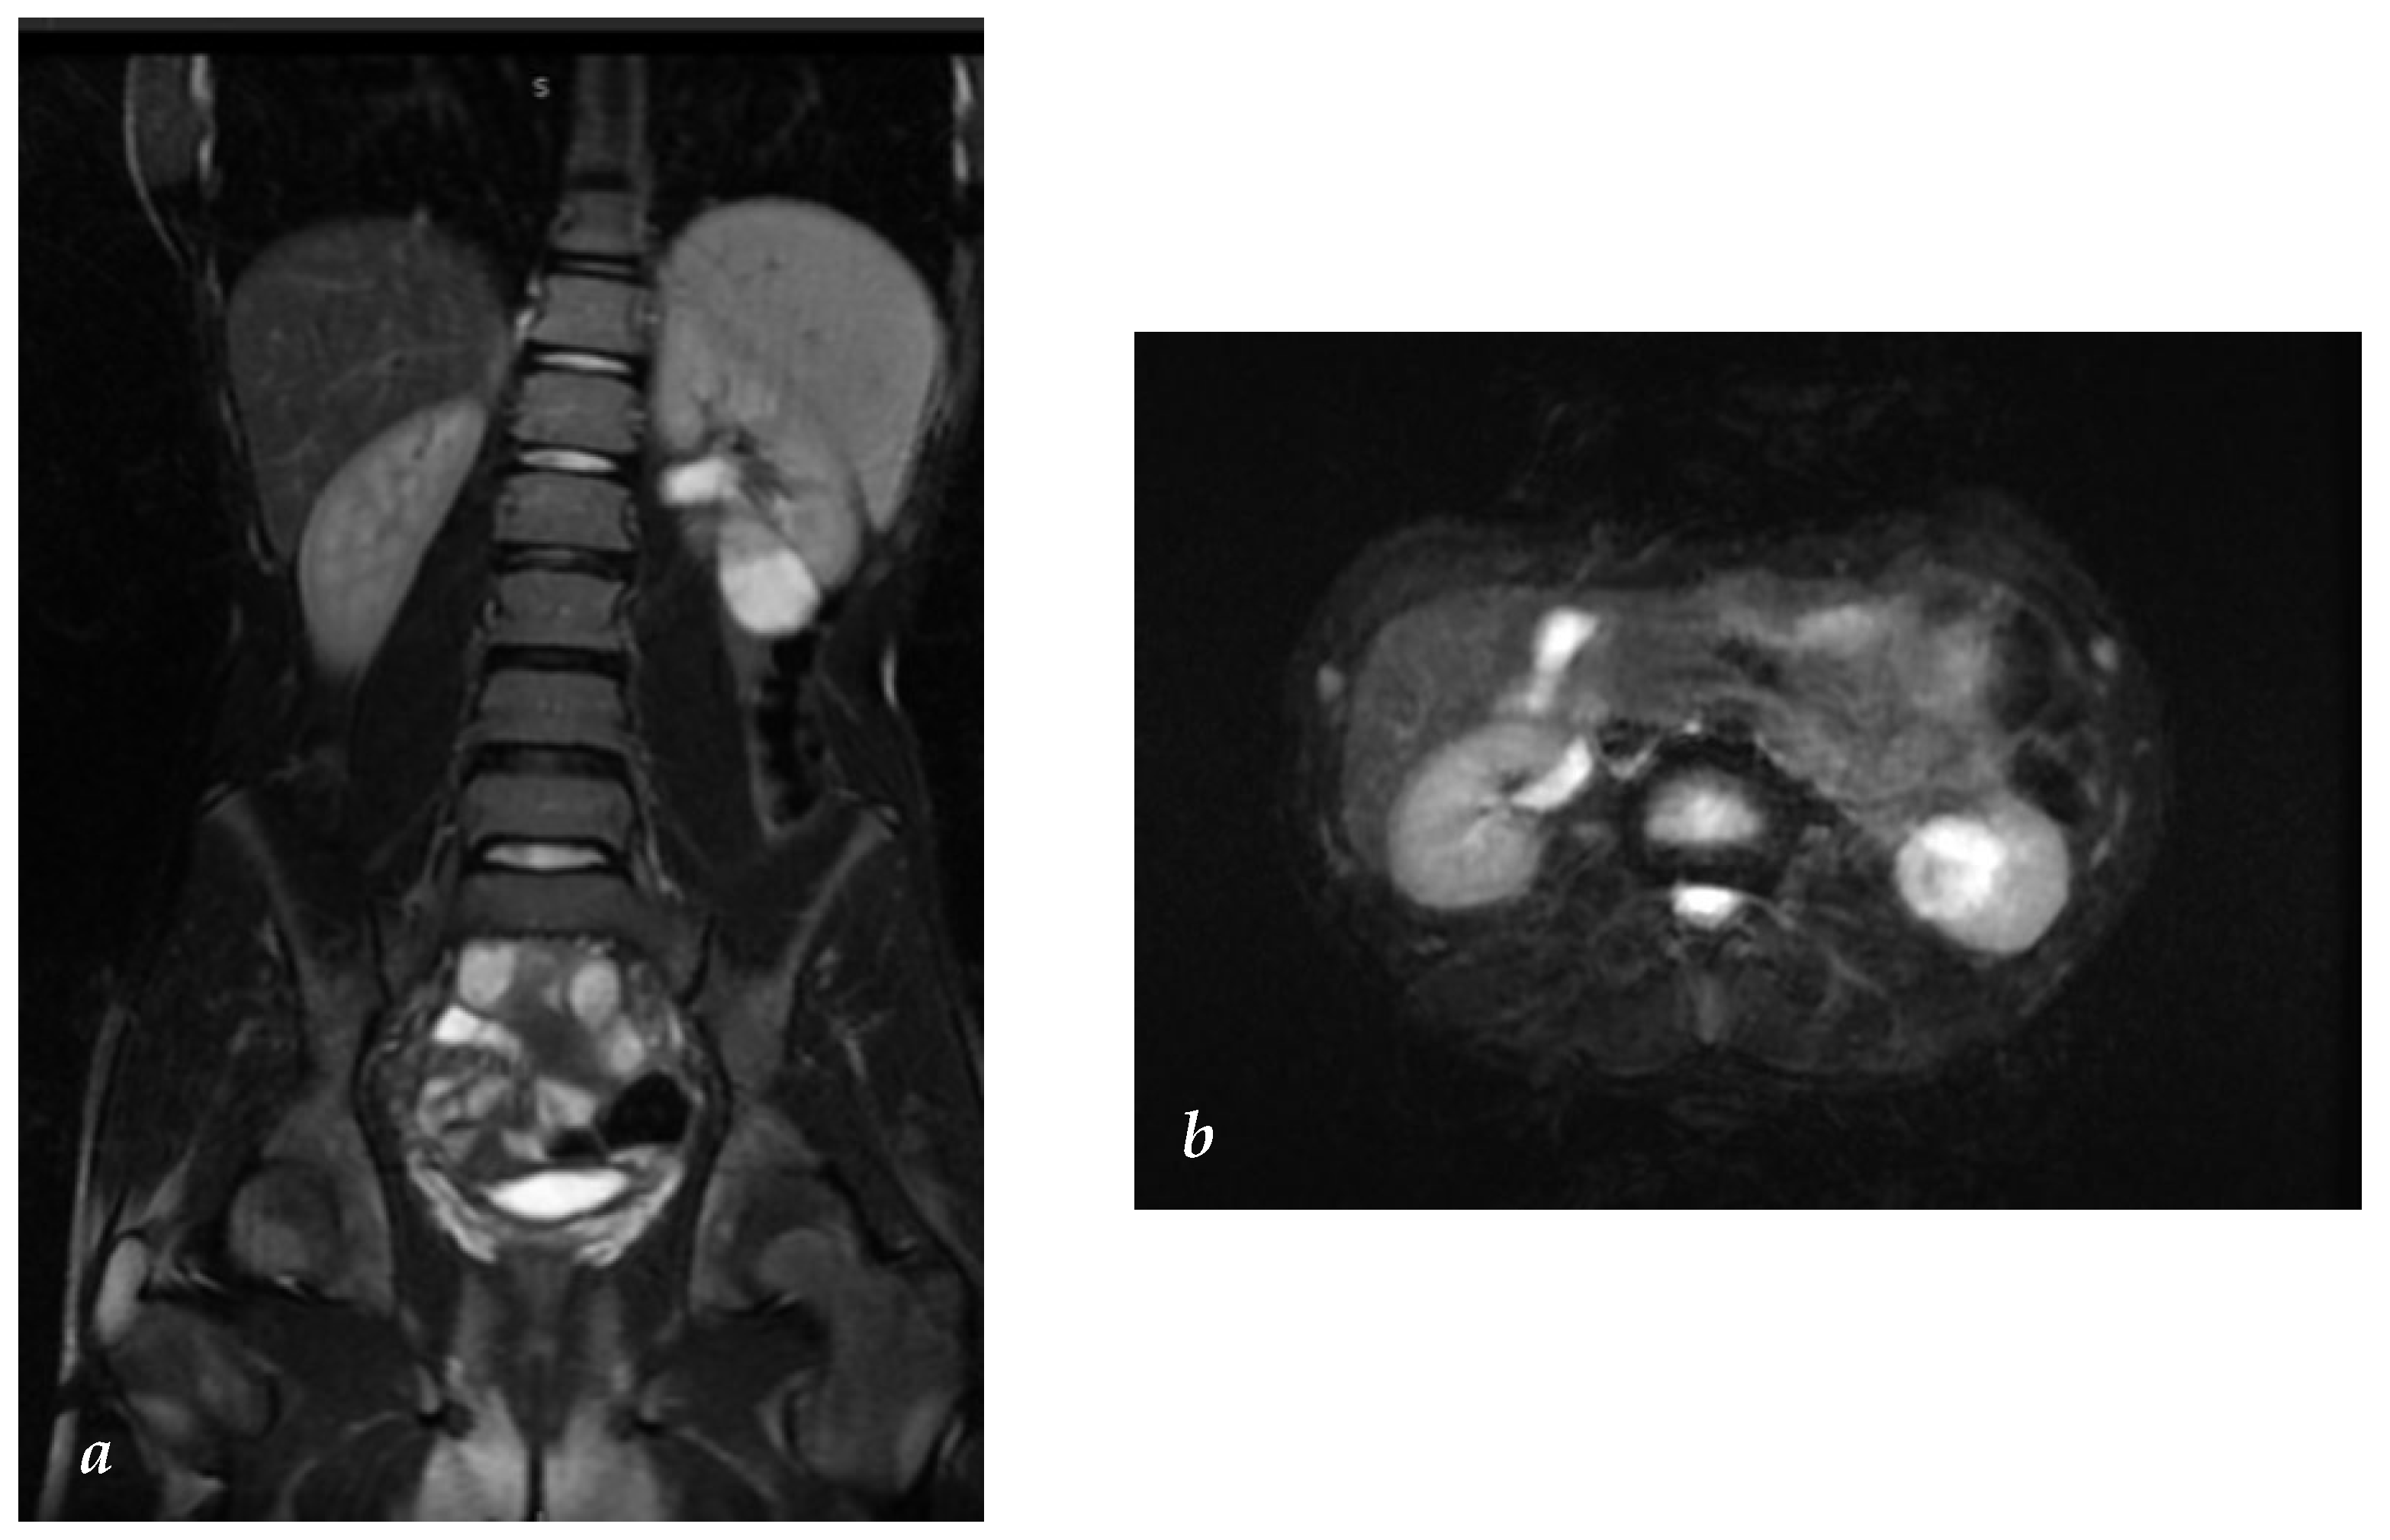

A 14-year-old boy with a left varicocele underwent an abdominal US (not recommended by the EAU/ ESPU guidelines), which incidentally revealed a hyperechoic round mass in the lower pole of the left kidney measuring 35 × 33 mm. Abdominal low-dose CT confirmed a partially exophytic lesion in the lower pole of the left kidney. The lesion exhibited a hypodense lower part suggestive of liquid content without contrast enhancement and a solid upper part with point-like calcifications and contrast enhancement. It was classified as a Bosniak III cyst (Figure 1a,b).

MRI was planned and, during the creatinine level measurement for the administration of an MRI contrast, complete blood count and electrolyte tests were requested, and they were within normal ranges. The MRI revealed a partially solid upper portion and a fluid-filled lower portion of the lesion in both T1 and T2 phases, resulting in the upgrade of the Bosniak classification from III to IV (Figure 2). A chest CT scan did not exhibit any suspected findings.

Figure 2. (a,b) Abdominal MRI: the coronal and transverse views exhibiting the tumor position and excluded lymph node localization.